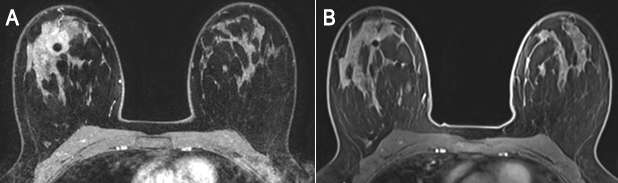

Management of Patients Undergoing Neoadjuvant Therapy

Breast MRI is indicated in patients undergoing neoadjuvant therapy (chemotherapy prior to surgery) to assess disease response. The tumor measurement is most accurate on MRI, as sonography and mammography typically underestimate tumor size. Therefore, breast MRI is the most accurate imaging modality to assess tumor response, with a positive predictive value of 93%6. Imaging the patient before treatment and after completion of one to two cycles can help predict how well the patient is responding to neoadjuvant therapy. In patients who do not respond, MRI after completion of the regimen can be performed to identify and localize residual tumor5.